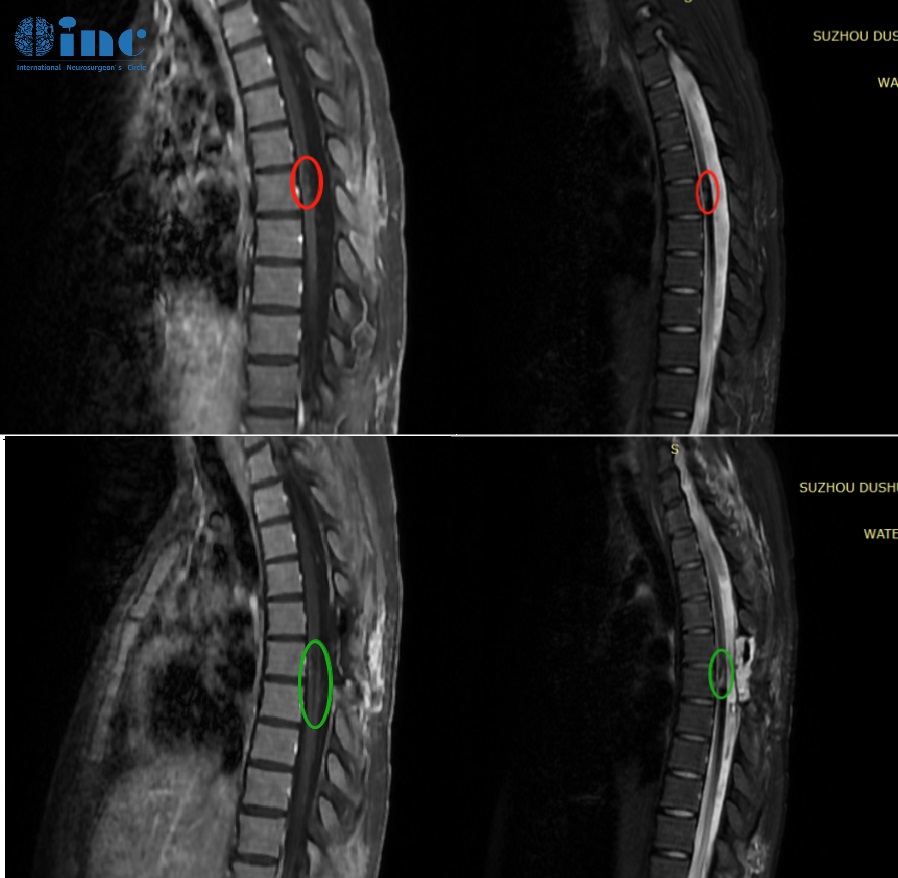

21岁女孩-胸髓髓内海绵状血管瘤

简要病史:还在读大学的田田在一次参加完常规体育运动后自感后背轻微疼痛,两天后出现双下肢无力,检查诊断胸髓髓内出血性病变。后续病情进展很快,还出现小便困难,双下肢无力加重等症状。再次检查后确诊胸髓髓内6段海绵状血管瘤,医生考虑血管瘤位置比较深,在腹侧,手术风险大,建议保守治疗。远程咨询巴教授后,教授表示这次手术的目的是把现在存在的血管瘤拿掉。

治疗过程:3月24日,在苏州独墅湖医院,巴教授顺利为田田顺利手术。

术后情况:术后一天ICU查房田田意识清醒,交流正常。右腿伸直略微困难,脚趾活动正常。术后五天普通病房查房田田感觉很好,右腿活动正常,双腿肌力正常。术后两周情况目前田田术后两周,已经可以下床行走活动,术前的症状有所缓解。术后两个月情况:田田正在稳定康复训练中。

术后两个月时,田田正在康复医院进行康复训练